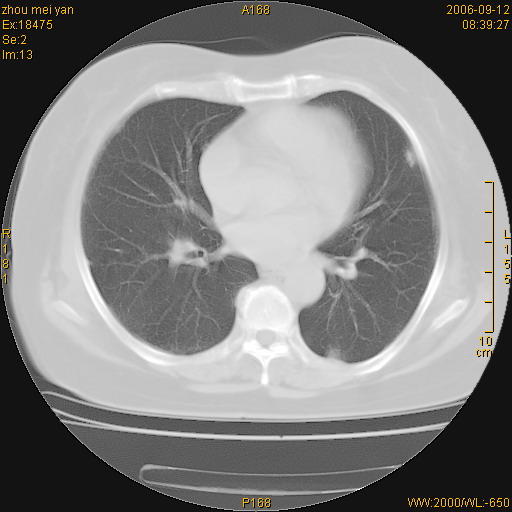

患者、女、55岁。因心率失常住院检查ct发现胸部多发结节。腹部b超肝、胆、胰、脾、肾、子宫附件未见异常。无结核病史,无粉尘接触史。请大家来会诊。谢谢!

病变位于胸膜,多发结节,边界清楚,内见小结节状钙化。其它未见异常。

多发胸膜表面的结节,基本对称,部分有钙化。首先考虑类风湿性胸膜结节,次则考虑结核性胸膜炎后遗之胸膜结节状增厚、钙化。

双侧胸膜多发结节,形态不规则,边缘较清楚,每一个结节中心似乎都有钙化点的特征,与胸膜广基相切。临床无结核病史,无粉尘接触史。

影像表现十分有特点:双侧肋胸膜及膈胸膜广泛散在分布大小在2至6mm左右,较大病灶中心可见钙化。

双侧肋胸膜及膈胸膜广泛散在分布大小不等结节影,较大病灶中心可见钙化。